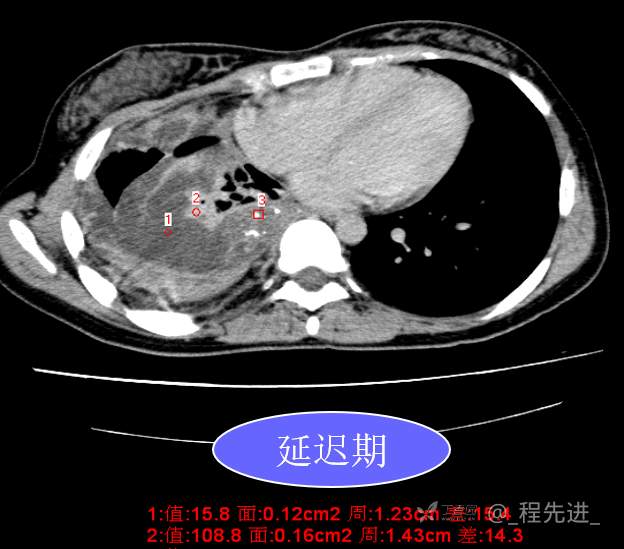

患者性别:女

患者年龄:26岁

简要病史:反复胸闷、气喘、咳嗽半年